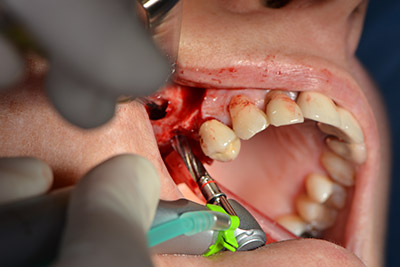

Die anschließenden Bohrungen werden mit einer reduzierten Umdrehungszahl von 300/min durchgeführt. Hier zeigt sich einer der Vorteile der Implantmed. Das chirurgische Protokoll kann voreingestellt werden – die einzelnen Positionen sind über einen einfachen Druck auf die Position „P“ der Fußsteuerung anwählbar. (Abb. 10 bis 11)

Die nächste programmierte Position ist bereits die Implantateinbringung und in unserem Hause mit einer Kraft von 32 Ncm voreingestellt (Abb. 12).